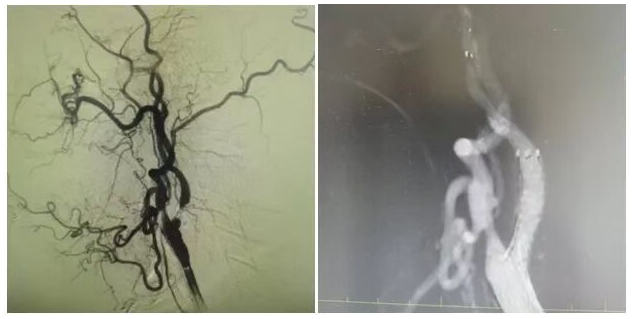

為明確病因,團隊為姜大爺安排針對性檢查:頭顱 MRI 彌散成像顯示左側(cè)大腦半球有分水嶺性腦梗死,提示腦組織缺血損傷,頸部 MRA 檢查發(fā)現(xiàn)左側(cè)頸內(nèi)動脈起始處重度狹窄,血流信號減弱。隨后的 DSA(數(shù)字減影血管造影)檢查進一步明確,左側(cè)頸內(nèi)動脈起始處狹窄程度超 90%,呈 “閉塞前改變”,血流受阻導(dǎo)致左側(cè)大腦半球供血不足,進而引發(fā)腦梗死與抽搐。

手術(shù)當天,丁金明主任親自操刀,團隊默契配合:在姜大爺右側(cè)腹股溝穿刺股動脈置入動脈鞘,沿鞘送導(dǎo)絲和導(dǎo)管,在 DSA 引導(dǎo)下穿過狹窄部位,用球囊預(yù)擴張后,精準釋放頸動脈支架。術(shù)后 DSA 顯示左側(cè)頸內(nèi)動脈血流通暢,狹窄解除。手術(shù)歷時 1 小時,姜大爺生命體征平穩(wěn),無并發(fā)癥。